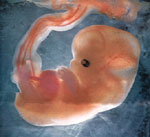

6 weeks

8 weeks

11 weeks

Did you know that at 2 months the baby has become sensitive and responds to touch. All five major areas of the adult brain are present. Brain functioning, as measured by EEG waves, has been recorded as early as 6 weeks. The baby is about 2 1/2 inches long and about 3/4 oz.  It is very expressive, wrinkling its forehead, turning its head and opening and closing its tiny lips.